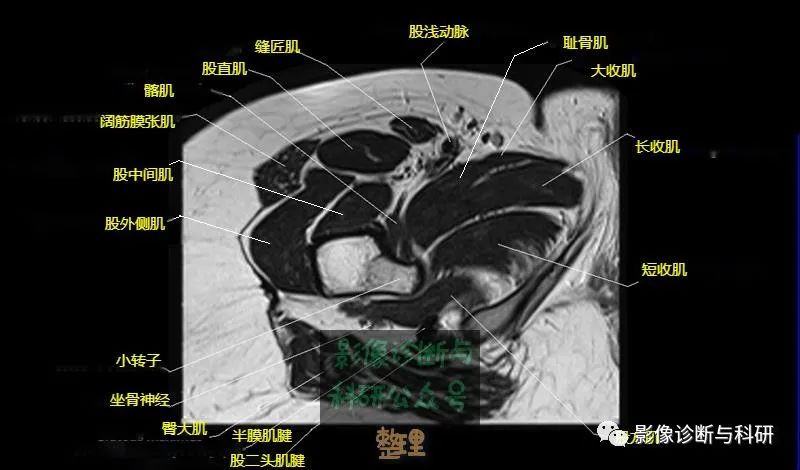

髋关节MR轴位详细标注

大腿肌配布于股骨周围,分前、后和内侧三群

前群

位于大腿前面,有缝匠肌和股四头肌。

内侧群

位于大腿内侧,共5块,其中股薄肌位于最内侧;另4块分三层,浅层靠外上方为为耻骨肌,下方为肌长收肌。长收肌深面是第二层的肌短收肌。第三层是强有力的大收肌。这一群肌均起自耻骨支和坐骨支,除股薄肌止于胫骨上端内侧外,其余各肌都抵止在股骨粗线。

后群

位于股骨后方,包括股二头肌、半腱肌和半膜肌。